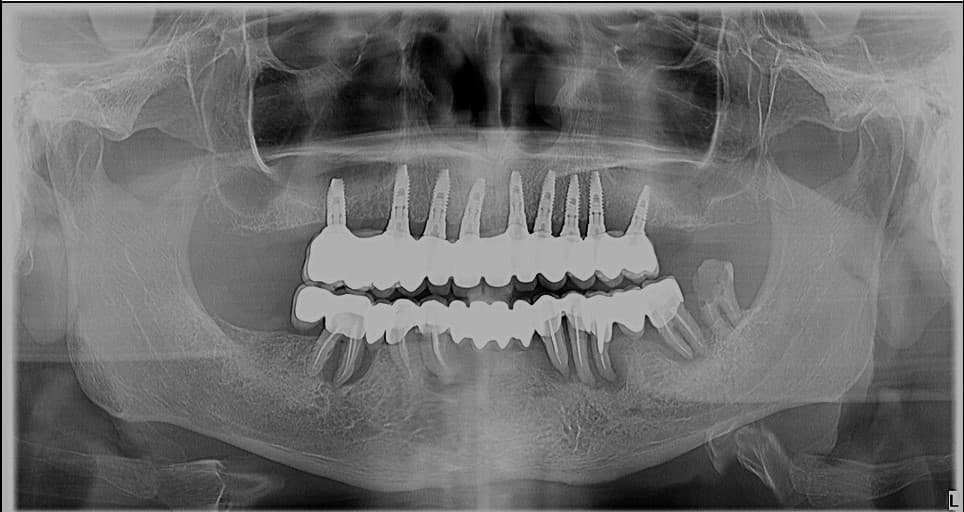

Stomatologia integrativă pune accentul pe sănătatea întregului corp, considerând cavitatea bucală ca parte integrantă a acestuia. Cercetările și practica clinică au demonstrat o legătură puternică între sănătatea orală și starea generală de sănătate a organismului.

Această abordare holistică ia în considerare efectele pe termen lung ale tratamentelor stomatologice, adresând cauzele fundamentale ale problemelor dentare și oferind tratamente conservatoare non-invazive.

- Coroane, punți și fațete din ceramică monolitică/presată sau zirconiu